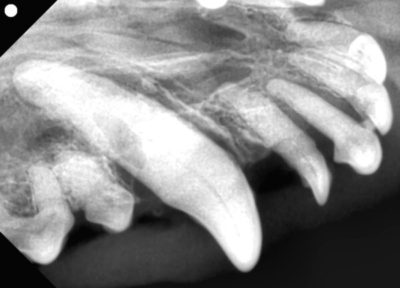

右上の犬歯

黄色斜線部が歯周病で周りの骨が溶けてしまっている状態。口腔鼻腔ろうになっていた。

歯科レントゲンでも犬歯の一部に欠損があるのがわかりますね。これは頭部レントゲンで撮影した部分と一致します。